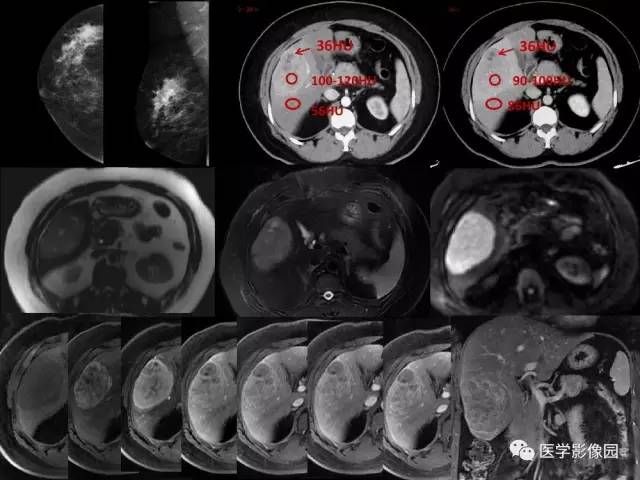

乳腺癌+肝脏神经内分泌肿瘤1例CT及MR